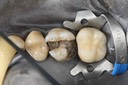

Mark Chun #14 pre-op

Mark Chun #14 caries removal